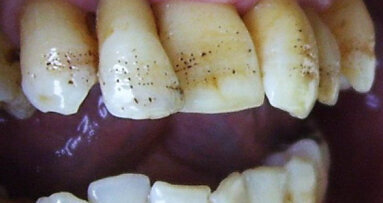

Clinically, gingival enlargement is presented as painless, firm, nodular expansion of interdental papilla. It is a generalised condition, but is more severe in the maxillary and mandibular anterior segments. Gingival enlargement occurs in proximity to the teeth and not in toothless jaw sections. Drug-induced gingival overgrowth can occur in sites with minimal or no plaque, but it interferes with oral hygiene and may often lead to chronic inflammation, which complicates the enlargement. In cases with secondary gingival inflammation, the gingiva is bluish-red in colour, with a lobulated surface and a tendency for bleeding.(7)

Two patients aged 67 and 73 with complaints of gingival enlargement were referred to the department of Periodontology, Medical University, Plovdiv. Besides gingival hyperplasia, they reported also bleeding gums, halitosis and inability for good oral hygiene. The patients’ medical history revealed systemic use of ACE inhibitors (Prestarium 2.5 mg and Co-Enalapril 20mg/12.5mg) for antihypertensive treatment.

The intraoral examination revealed generalised, grade II gingival enlargement(20) in the anterior segment of the mandible (case I and case II) and the maxilla (case II). There was a high score of debris and calculus index according to Greene-Vermillion index.(21) The gingiva showed signs of inflammation as redness, bleeding on probing and suppuration. Halitosis was also detected. The measurement of pocket probing depth revealed deep pockets of about 7-8 mm (Figs. 2-14).